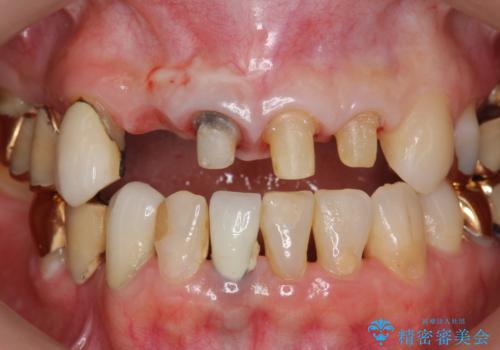

- 前歯の痛み・排膿・ぐらつきの改善を求めて来院されました。

視診・X線写真検査より根尖性歯周炎が認められ再治療が必要な状態です。

再根管治療を行うべくクラウン除去を行ったところ、右上側切歯に保存不可能な垂直性の破折が認められたため抜去が必要になりました。

即切歯の抜歯を行う場合犬歯を含めたブリッジによる補綴計画を立てることが多いですが、今回は犬歯から大臼歯にかかる大きなブリッジが既に装着されていたため予算とご希望を相談し前歯のみの延長ブリッジ補綴で治療を行っていくこととしました。